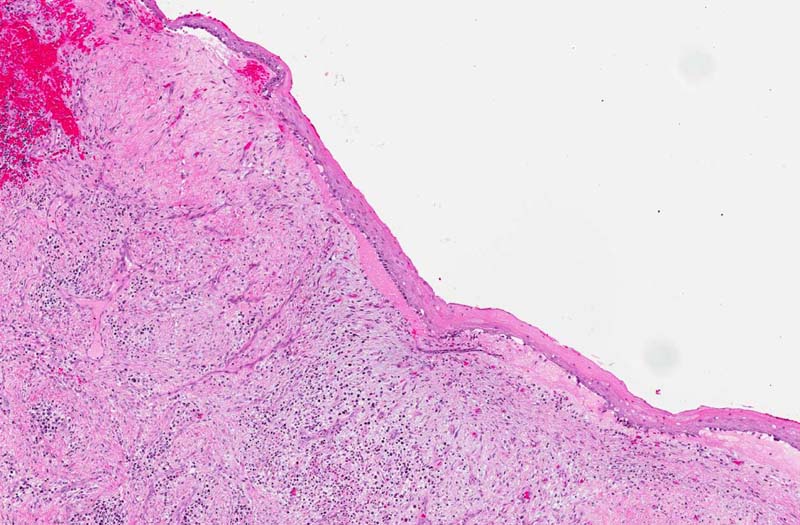

Hematoxylin & eosin

Area 3: The ulcerated area is lined by a mixture of chronic inflammatory cells including lymphocytes and plasma cells. Also present is formation of new blood vessels.

• In some are of the specimen, there is chronic ulcer and inflammatory changes and not covered by epithelium. This finding reflects the inflammatory nature of the patient's clinical condition. Although this type of cysts typically have mild to moderate inflammation in the cyst wall, ulcer associated with intense inflammation is not a classic features and the inflammation here is most likely resulted from infection.